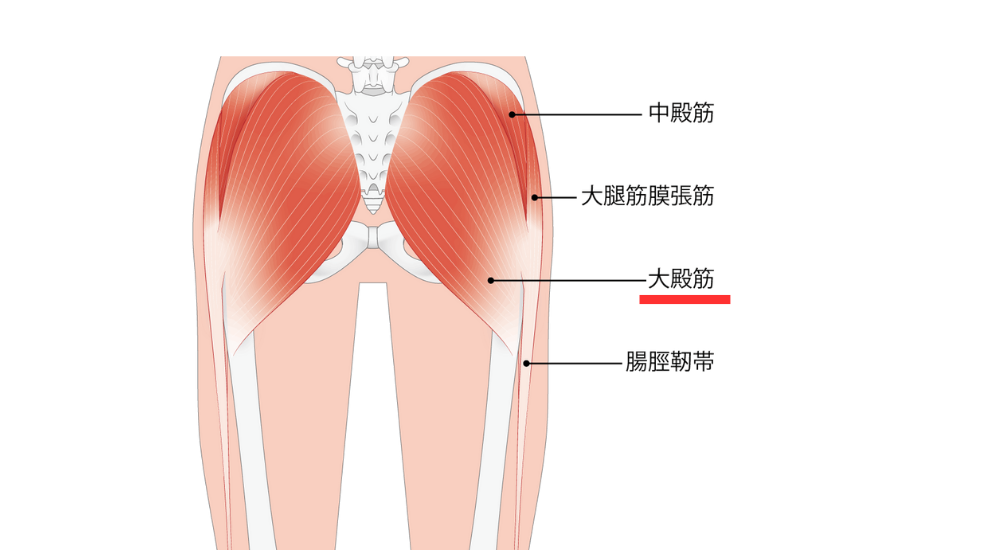

- 大殿筋(特に大腿直筋): お尻の筋肉。この筋肉が弱くなると、反り腰になります。